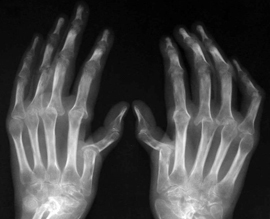

Представлена новая схема лечения ревматоидного артрита

На начальных стадиях ревматоидного артрита тройная базисная терапия помогает значительно улучшить состояние пациентов, показали результаты нового исследования. Стандарт лечения ревматоидного артрита предполагает, что пациентам с впервые диагностированным заболеванием нужно назначать метотрексат для монотерапии или в комбинации с другими базисными противоревматическими препаратами, независимо от приема препаратов глюкокортикостероидов.

Если за 3 месяца лечения нет улучшения или в течение 6 месяцев ремиссия не достигнута, терапию меняют. Но результаты нового исследования Treatment in the Rotterdam Early Arthritis Cohort показали, что эти рекомендации стоит пересмотреть.

В ходе эксперимента с участием 281 пациентов, принимавших метотрексат при ревматоидном артрите и глюкокортикостероиды, разделили на две группы. Одни участники принимали сульфасалазин и гидроксихлорохин, а другие - плацебо. Спустя 3 месяца в группе пациентов тройной базисной терапии выявлено более раннее начало ремиссии, чем в группе метотрексата. Через 2 года ремиссия ревматоидного артрита продолжалась примерно у половины пациентов в каждой группе. При достижении ремиссии дозы лекарств постепенно снижали.

Использование нового стандарта лечения ревматоидного артрита дает надежду, что пациентам не придется всю жизнь принимать препараты, а можно будет постепенно снижать дозы до полной их отмены. Но вопрос безопасности новой схемы лечения ревматоидного артрита пока остается открытым, подчеркивают ученые из Университета Эразма.